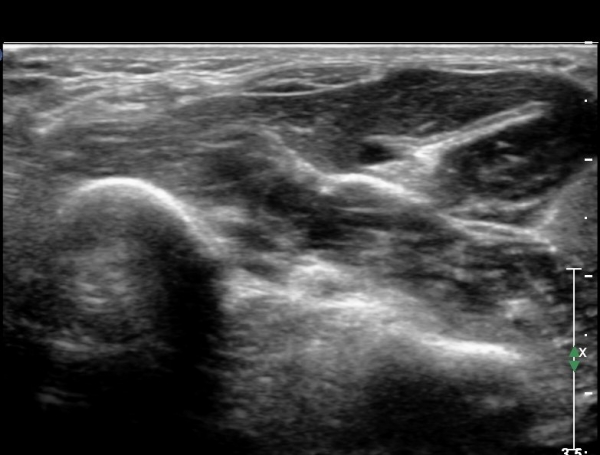

¾Æ·§ÆÈ ÇϺκΠȾ´Ü¸é°Ë»ç¿¡¼­ Àü°ñ°£ ½Å°æ Áö¹è¸¦ ¹Þ´Â  PQ ¿¡¼­ ½Å°æ¸¶ºñ ¼Ò°ß(°í¿¡ÄÚ ±ÙÀ§Ãà)À»

º¸ÀÌÁö ¾ÊÀ¸³ª  FPL ÈûÁÙÀÇ Àú¿¡ÄÚ ºÎÁ¾ÀÌ °üÂûµÇ°í(»çÁø 2, 3) ³»°íÁ¤¹°ÀÌ FPL °ú Á¢ÃËÇϰí ÀÖÀ½ÀÌ °üÂûµÊ(»çÁø 3)